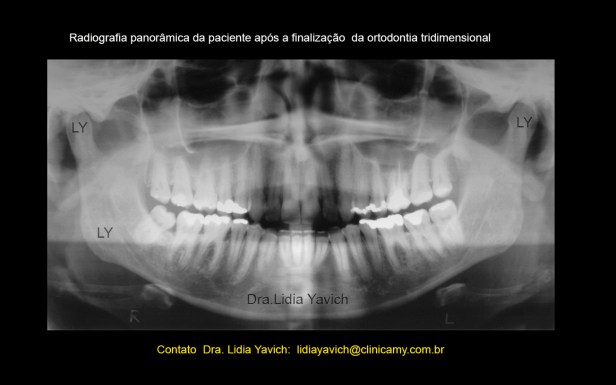

Radiografia panorâmica da paciente após a finalização da segunda fase, neste caso a ortodontia tridimensional.

Radiografias panorâmicas da paciente comparativas: 1 antes do tratamento, 2 durante a primeira fase, 3 durante a ortodontia tridimensional, 4 após a finalização da ortodontia tridimensional.